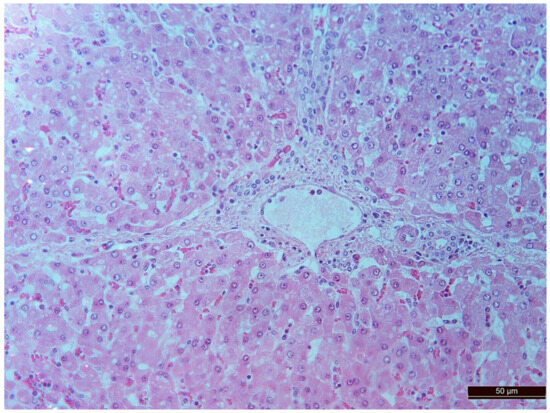

3.2. Pathology of the Liver